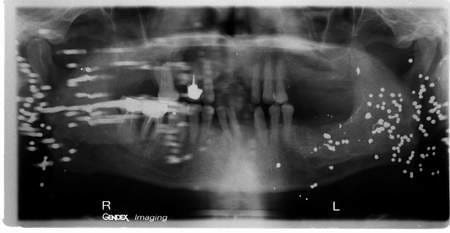

je vois un patient en urgence vendredi dernier,abcès sur 17.

On fait pano je mets sous ab et je revois mercredi pour extraire.

La première pano était comme la photo jointe.

Ce soir j'ai extrait la 17 , et j'ai dit au patient:"petit souci avec la radio, il ya une zone pas très nette je vous la refais.

Le résultat?????

La même chose exactement.

Je précise qu'entre temps, évidemment j'ai fait d'autres panos parfaites avec le même film!!!!

Au passage j'ai vu qi'il avait ce soir des petites tâches sur le visage, je lui ai demandé s'il faisait de la peinture en ce moment, il m'a dit oui je repeins chez moi et j'en arrive.

Mais les tâches sont au même endroit depuis vendredi!!!

On a deja vu des panos comme ca qui marquent une sequelle d'impacts ballistiques (des plombs de chasse ou BB gun).

Mais en general c'est d'un cote de la face. Alors que la c comme un spray!?

microgouttelettes de peintures sur la peau tout simplement, et deformation radio pour les trainées

Vu le groupement, c'est pas tiré loin.

Si il a des marques sur la peau c'est que c'est pas tiré au fusil , les plombs auraient traversé à cette distance(et en plus les plombs seraient écrasés ).

Ce qui est bizarre c'est les impacts des 2 côtés, cest drôlement dispersé . Comme Dumaille : pistolet à grenaille avec canon goupillé ...

Aucune cicatrice !!!